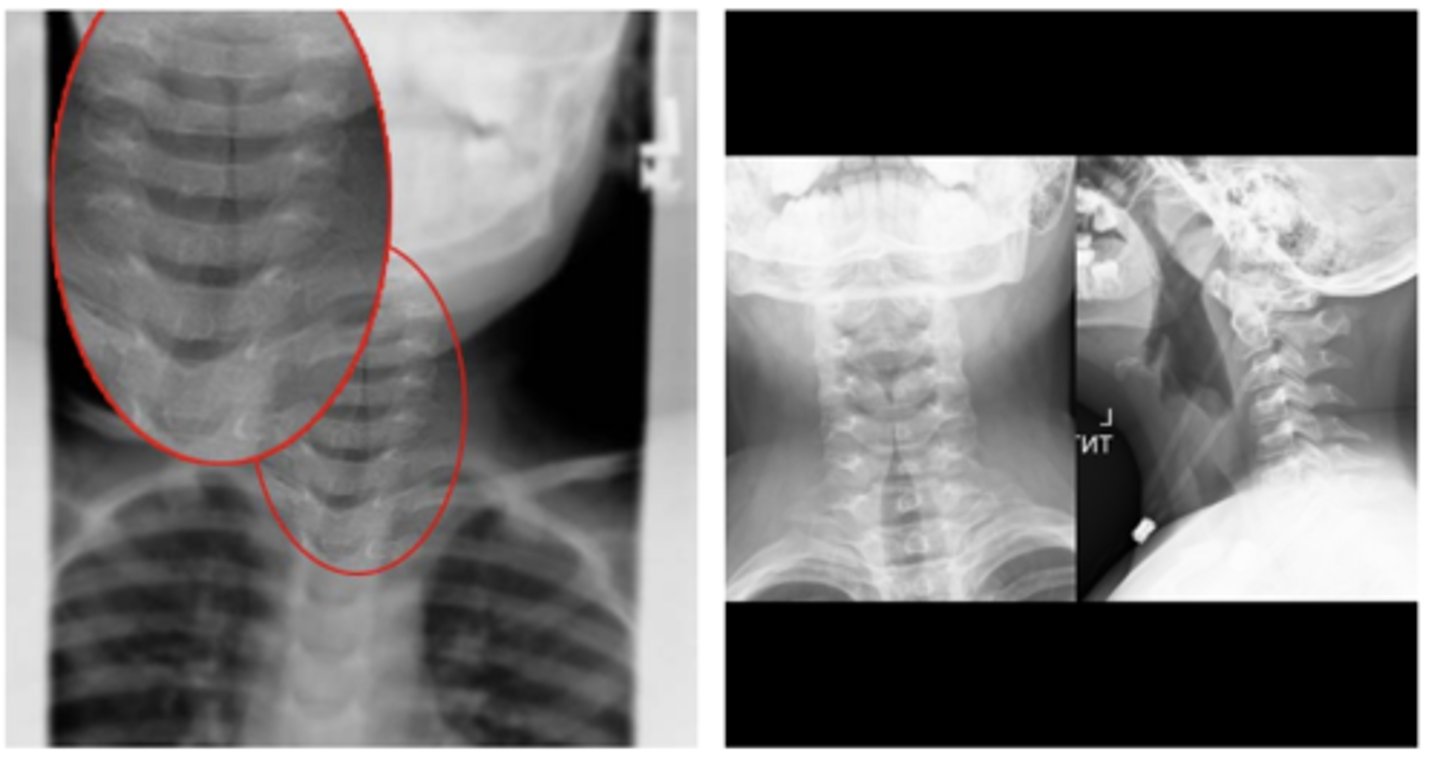

New cards

thumb sign (L)

-indicates inflammation of epiglottis

Classic radiologic finding for epiglottitis (ID L or R)

<p>Classic radiologic finding for epiglottitis (ID L or R)</p>

Croup "steeple's sign"

oNarrowing of the trachea due to edema

oCauses: Respiratory Syncytial Virus, Human parainfluenza virus (HPIV-1)

ID abnormality - what dz is this indicative of?

<p>ID abnormality - what dz is this indicative of?</p>